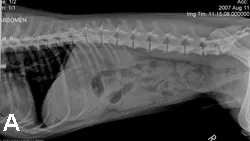

Testing should include survey radiography and abdominal ultrasonography. In this case, abdominal radiographs showed dilation of the stomach with a fluid density (Figure 1). Abdominal ultrasonography showed a very dilated and fluid-filled stomach and a proximal duodenum that exhibited little motility and contained an intraluminal foreign body (Figure 2). The foreign body had a hyperechoic surface with distal acoustic shadowing. The intestines distal to this object were normal.

Figure 1. Lateral (A) and ventrodorsal (B) abdominal radiographs showing dilation of the stomach with a fluid density and a focal gas dilation of the intestinal tract i n the right upper abdominal quadrant.